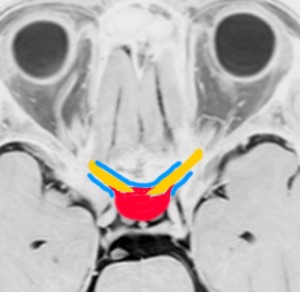

大後頭孔(大孔)髄膜腫 foramen magnum meningioma)

この腫瘍はfarlateral approachなどの頭蓋底手術をしなくても,外側後頭窩開頭で全摘出できます。要領は,S状静脈洞の下端の周囲骨を削除することです。大後頭孔髄膜種は延髄を圧迫するので巨大なものはありません。出血のコントロールや延髄からの剥離は比較的容易なものが多いでしょう。舌咽神経と迷走神経損傷を避けることが重点となります。

迷走神経と舌咽神経は機能温存できました。舌下神経が腫瘍の表面に薄く広がり剥がすことができずに半分以上を切断しています。でも片側舌下神経麻痺では日常生活に困ることはあまりありません。